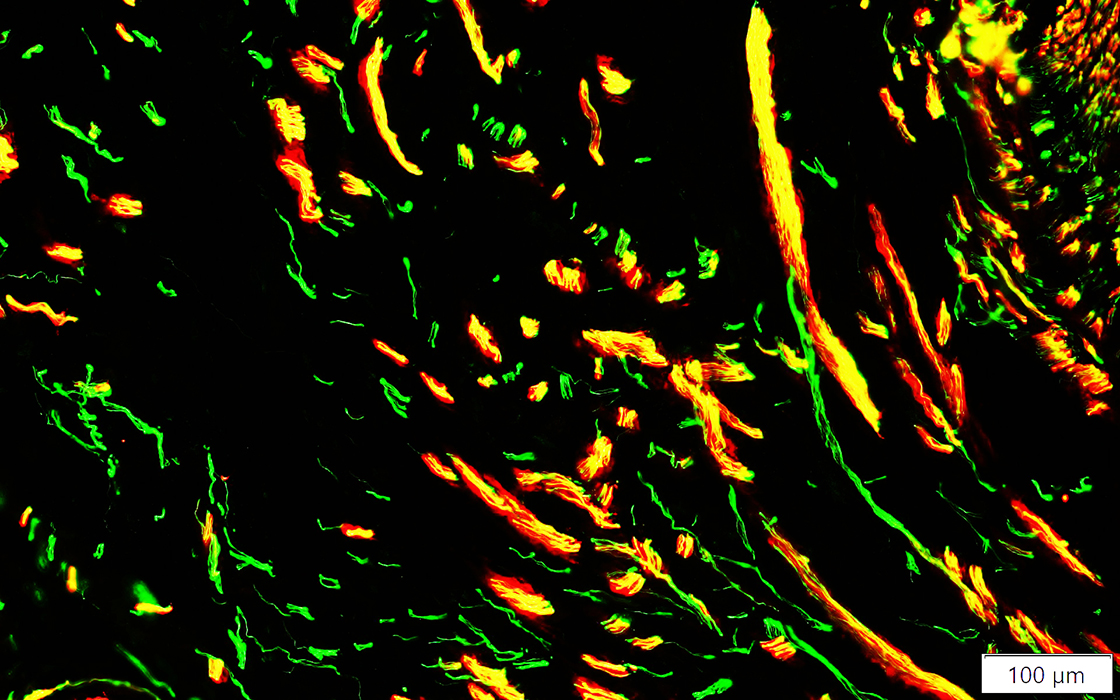

Neurofilament (Green); NCAM (Red)

NCAM

Present in Schwann cells around most axons in Neuroma (Left) & surrounding axon sprouts (Right)